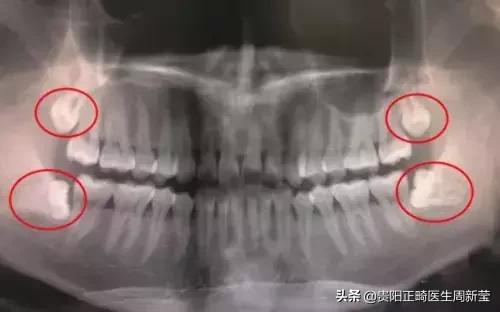

从功能上来讲,第三磨牙属于多余的牙,28颗牙已经可以满足现代人的需求。而且,由于智齿萌出较晚,往往没有足够的位置,智齿很少有能长好的,要么长不出来,要么长得不正。

长不正,就是指智齿不能以正常的姿态长出来,它很可能倾斜,把正常的牙齿抵住了造成牙列不齐,甚至导致龋坏。对于长得不好的智齿,可以进行预防性拔除。